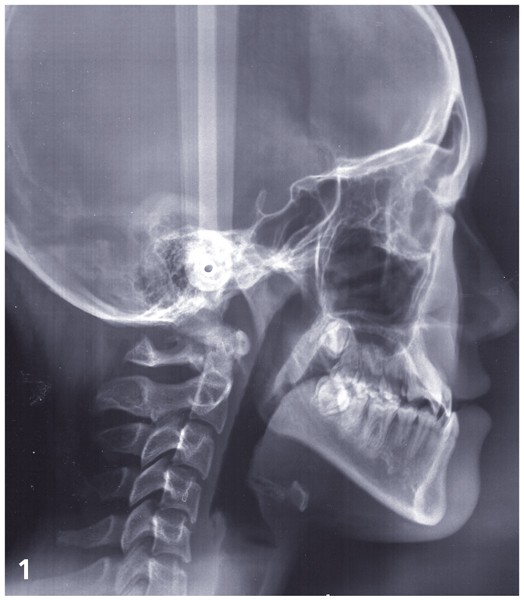

Sylvie se présente à l’âge de 15 ans avec une classe III squelettique (ANB -7,6°) d’origine maxillaire et mandibulaire sur un schéma facial à tendance hyperdivergent (FMA 31°) (fig. 1).

La classe III d’Angle et l’occlusion inversée s’accompagnent de signes de compensations alvéolo-dentaires : vestibuloversion des incisives supérieures (I/SN 114°) et linguoversion des incisives inférieures (IMPA 86°). L’encombrement à l’arcade maxillaire est important, souligné par des canines en infra-mésio-vestibulo-position.